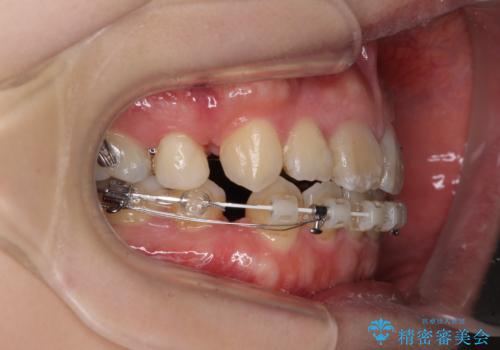

- ハーフリンガル

抜歯矯正が必要であることはご自身で理解されており、目立たない装置をご希望であったので、上顎が裏側装置であるハーフリンガル装置にて治療を行うこととしました。

開咬の改善には舌突出癖を改善するためのトレーニングが必要ですが、しっかりと行っていただき、想定よりも早い期間で治療を終えることができました。